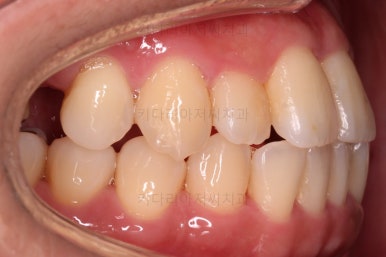

초진 시, 입안의 모습이에요.

결손부위가 눈에 띄고요.

결손부위가 양쪽에 있다보니 윗니 중간에 틈새가 벌어졌네요.

뒤쪽의 빈공간으로 치아들이 도미노처럼 쓰러져서 그렇습니다.

앞니의 약간의 틈새, 약간의 삐뚤어짐, 약간의 중앙선 틀어짐 등 심하진 않으나 약간씩의 문제점들이 있네요.

얼굴모습입니다.

약간의 돌출감 특히 아랫입술의 돌출감이 눈에 띄고요.

웃거나 말할 때 약간의 삐뚤어짐과 약간의 틈새가 심미성을 떨어뜨립니다.